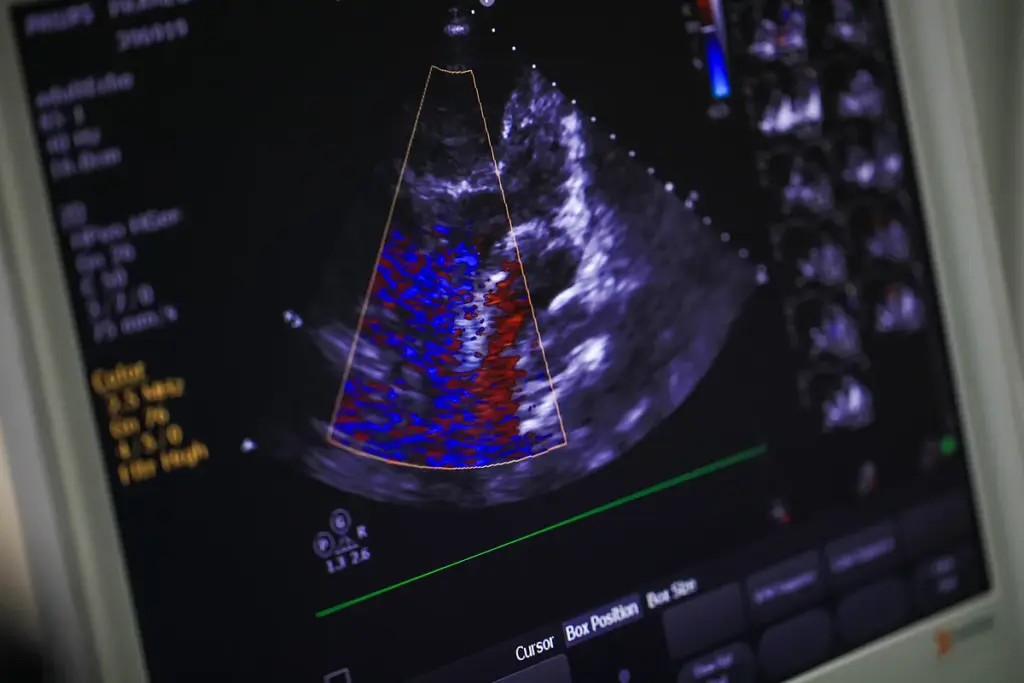

Essential Medical Tests Before Beginning Sports

Before starting any new exercise, some medical tests are needed to check heart health. These tests show how severe heart disease is and if there are heart disease symptoms.

- Electrocardiogram (ECG) to measure the heart’s electrical activity

- Stress test to evaluate heart function under physical stress

- Echocardiogram to assess heart structure and function

These tests give important info for a safe exercise plan. We stress the need for these tests to ensure safe exercise for heart conditions.